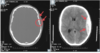

72

The most common risk factor for intracerebral hemorrhage is _

The most common risk factor for intracerebral hemorrhage is **hypertension**

77

Diagnosis?

Epidural hematoma

78

Most likely cause?

Rupture of the **middle meningeal artery**; often secondary to pterion skull fracture

79

Subdural hematoma

80

Etiology/cause?

**Rupture of bridging veins** (can be acute or chronic) * Hemorrhage crosses suture lines; poor prognosis

81

Subarachnoid hemorrhage

82

Bleeding due to trauma or rupture of aneurysm or AV malformation

83

Intraparenchymal hemorrhage

84

Most common etiology/cause?

Most commonly caused by **systemic hypertension**